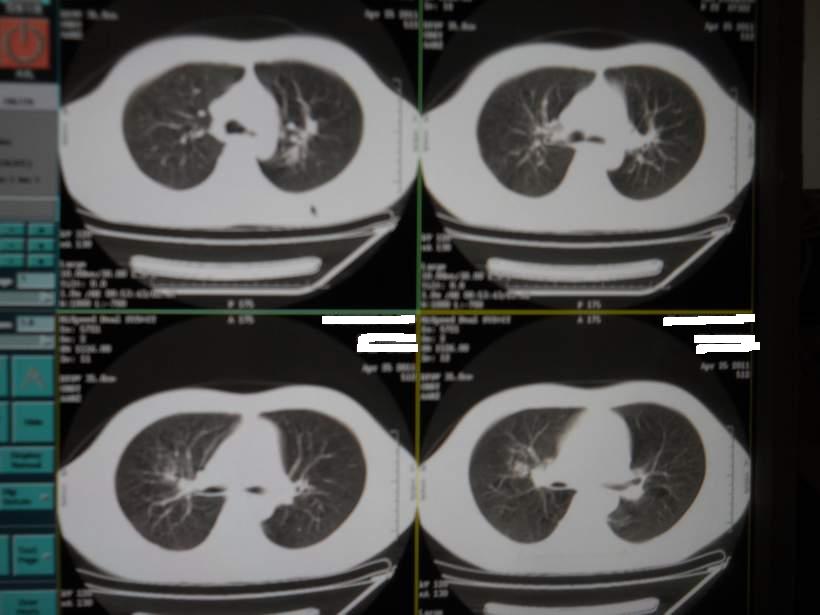

肺霉菌感染

男,22岁,一年前诊断马尔菲尼青霉菌感染,多次复查CT。多次HIV阴性。最近两次CT图片。有实验室结果。

最近实验室检查结果:霉菌感染。